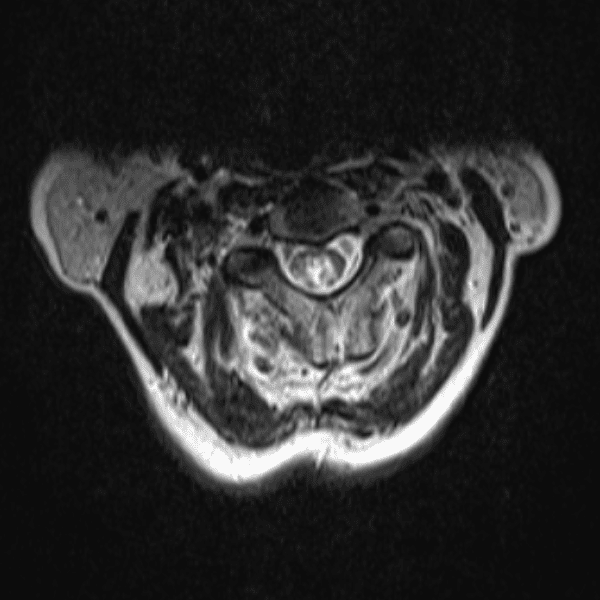

Simulates call by including subtle or difficult cases and some normals.

35 cases